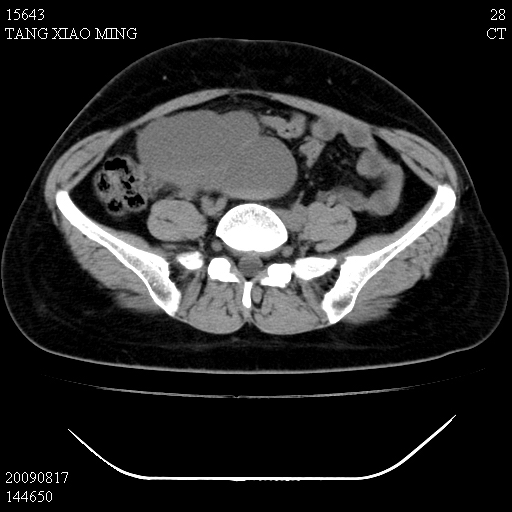

标题: CT21692:盆腔病变

女,33岁,右下腹痛2年余,既往宫外孕病史,如在我院手术,结果下周公布,

可能的诊断。1子宫内膜异位【子宫腺肌症并右卵巢巧克力囊肿】;2 右卵巢囊腺瘤。子宫肌瘤

1)考虑卵巢巧克力囊肿,不排除卵巢囊腺瘤。2)子宫肌瘤可能。

卵巢囊腺瘤,子宫肌瘤,直肠壁厚,不除外占位.